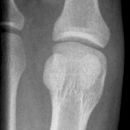

D1 Wachstumskerbe